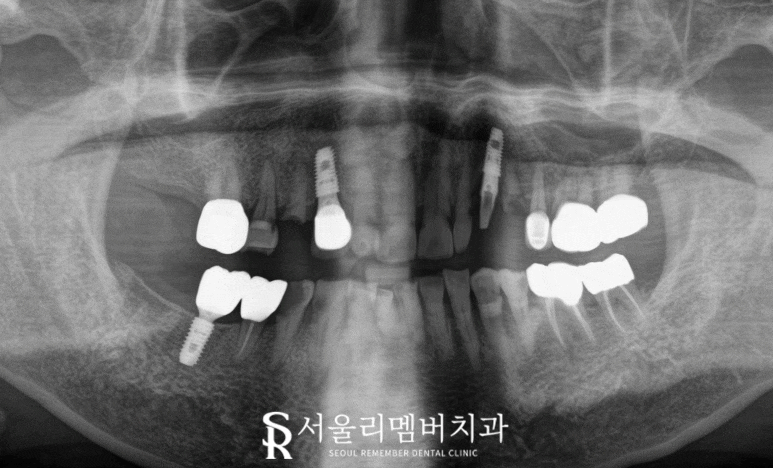

사당역 치과 에서는

다수의 문제가 존재한다면

엑스레이를 찍어

눈에 보이지 않는 곳까지

살펴봅니다.

이가 없는 곳에

남아있는 뿌리 조각은 없는지,

치아가 있더라도

뿌리 끝으로 염증은 생기지 않았는지

살펴봐야 정확한 진단이 가능합니다.

해당 케이스는 남아있는 전치부 치아에

심한 충치가 생겨있거나

곳곳의 이가 깨지고 빠져있습니다.

2024.05.14

또한 부러진 틈으로

음식 찌꺼기가 끼어

심한 구취와 통증을 유발하고

잇몸에 염증을 일으키고 있어 보입니다.